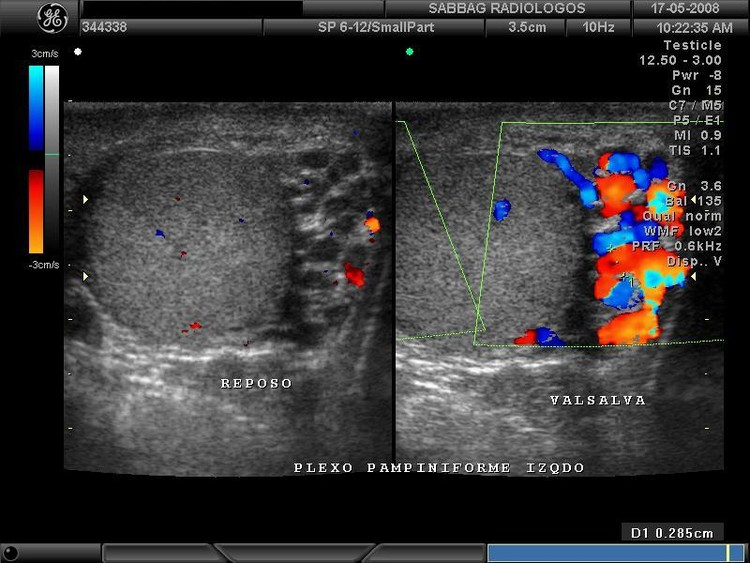

Para diagnosticar un varicocele hay que pensar en él y buscarlo durante la exploración física. Inicialmente, exploramos todo el contenido escrotal e inguinal con el paciente tumbado. Posteriormente indicamos al paciente que se ponga de pie y aumente su presión abdominal (maniobra de Valsalva), en este momento, si el urólogo tiene experiencia, detecta como refluye la sangre desde arriba y rellena el cordón inguinal y el plexo venoso testicular.

En la foto se aprecia una dilatación e ingurgitación de las venas del testículo izquierdo (varicocele izquierdo)

En el Instituto Urología y Medicina Sexual de Zaragoza, tras una exploración física cuidadosa, realizamos un estudio con ecografía-doppler color. Con esta técnica se aprecia correctamente si existe o no un varicocele y además nos permite realizar ecografía y estudio de los testículos.